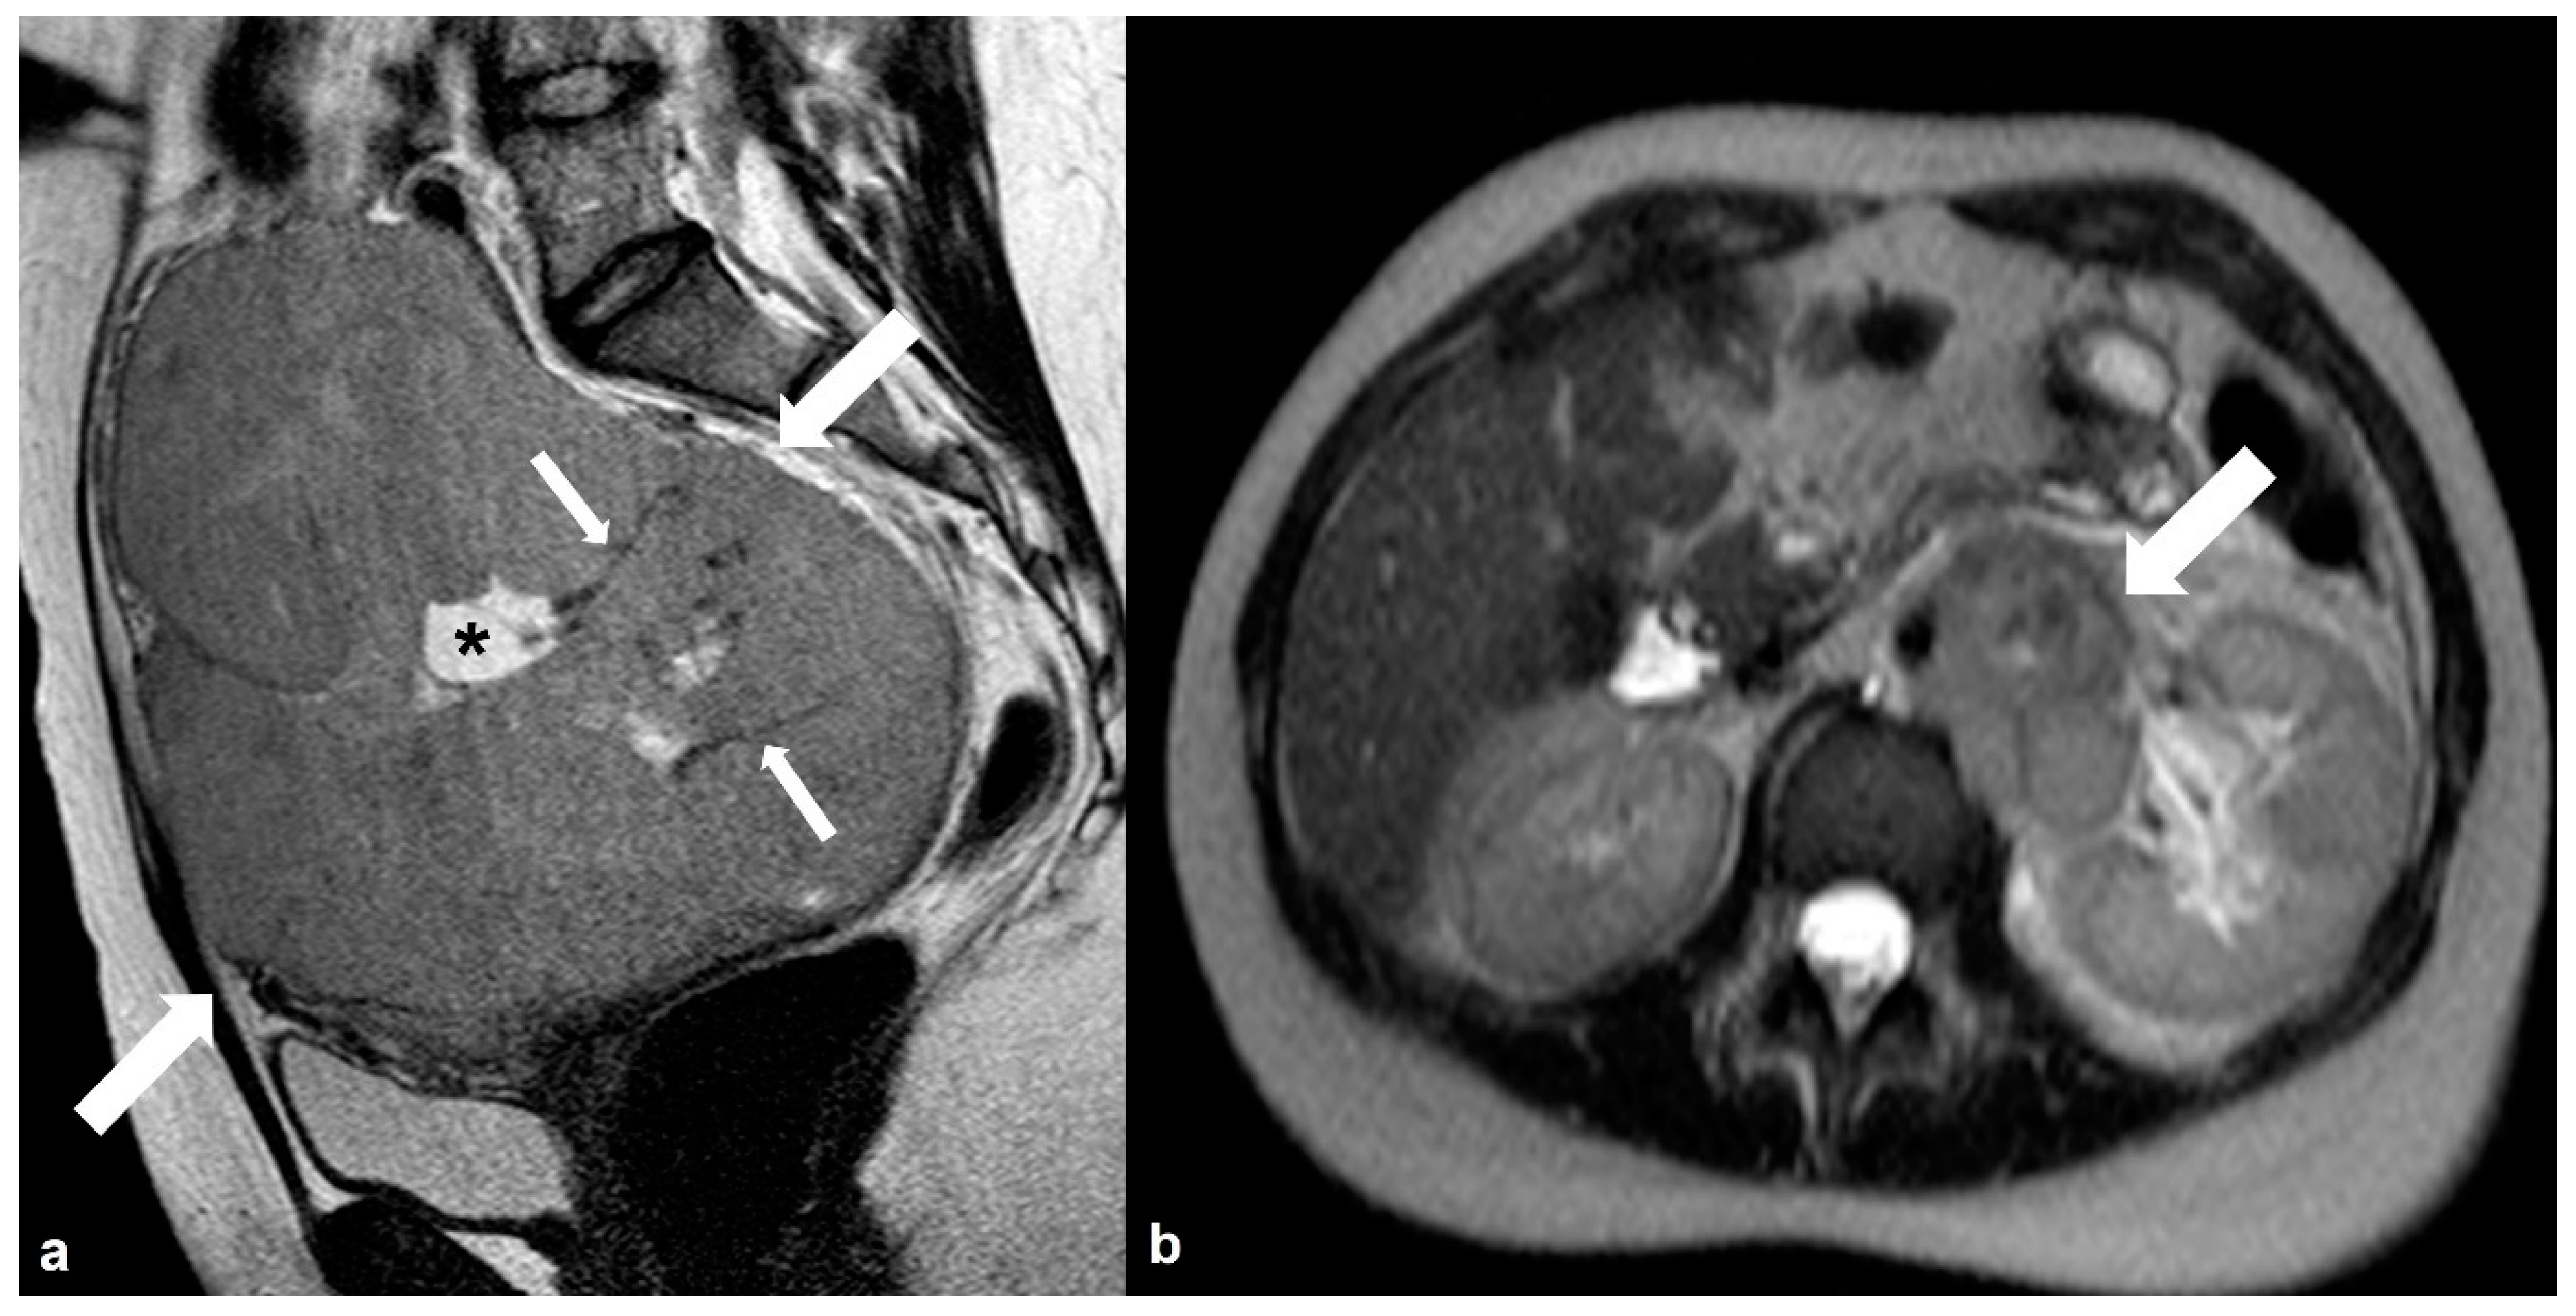

2.1.1. High-Grade Serous Cystadenocarcinoma (HGSC)

2.1.2. Serous Borderline Neoplasms and Low-Grade Serous Cystadenocarcinoma